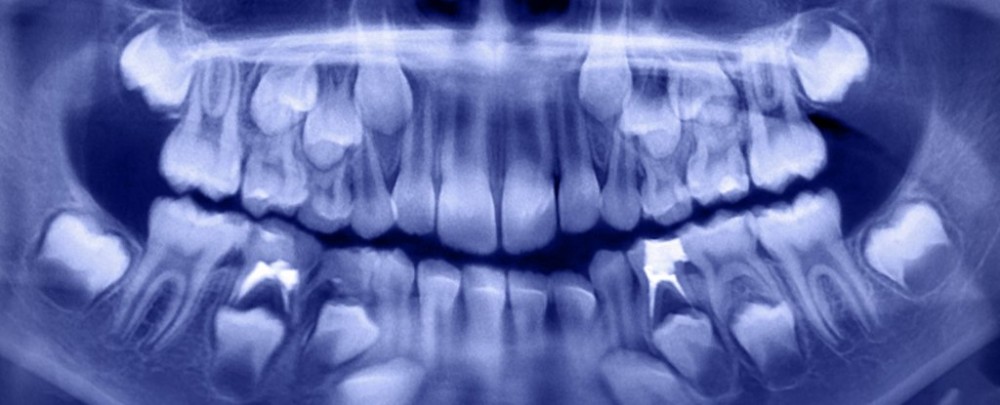

| Cậu bé ở Ấn Độ có tới hơn 500 chiếc răng trong miệng. (Nguồn: iStock) |

Các nha sĩ đã yêu cầu chụp X-quang và CT và phát hiện "cấu trúc giống như túi" trong miệng của cậu bé có chính xác 526 răng. Sự phát triển giống như khối u đã ngăn chặn sự phát triển răng hàm vĩnh viễn ở cậu bé.

"Răng có kích thước khác nhau, dao động trong khoảng 0,1 mm - 15 mm. Chúng trông giống như những viên ngọc trai trong một con hàu. Ngay cả những mảnh nhỏ nhất cũng có một lớp tráng men như một chiếc răng”, các bác sĩ cho biết.